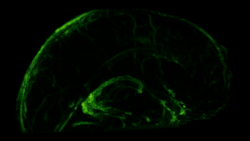

In transgenic mice containing Prox1-GFP or Vegfr3-LacZ reporter genes, the lymphatic vessels may be visualized by fluorescent microscopy or after X-gal staining, respectively.[2]

The meningeal lymphatic system is composed of a network of vessels along the dural sinus in the dura which express lymphatic endothelial cell marker proteins, including PROX1, LYVE1, and PDPN. The vessels extend along the length of both the superior sagittal and transverse sinuses and directly connects to the deep cervical lymph nodes.[1] These meningeal lymphatic vessels drain down and exit the skull along the dural venous sinuses and meningeal arteries. Meningeal lymphatic vessels also drain out of the skull alongside cranial nerves and through the cribriform plate. Molecular profiling indicates that the vessels are conventional lymphatic vessels: they express high levels of PROX1, LYVE1, PDPN and VEGFR3, but low levels of PECAM1. Meningeal lymphatic vessels absorb cerebrospinal fluid and drain into the deep cervical lymph nodes.[2]

Several unique attributes differentiate meningeal lymphatic vessels from lymphatic vessels in peripheral organs. Compared to peripheral lymphatic vessels, the meningeal lymphatic network is markedly less complex, with far less tissue coverage and lymphatic branching. Furthermore, meningeal lymphatic vessels are generally smaller than those in the periphery and display a structural homogeneity along the dural sinuses, remaining thinner and mostly unbranched along the superior sagittal sinus while growing larger and more branched along the transverse sinuses.[1] The meningeal lymphatic vessels are also unique for their scarcity of valves, which prevent back-flow of lymph. While the vessels in the superior parts of the skull were mostly devoid of valves, the larger lymphatic vessels of the basal parts only contain scattered valves.[2]